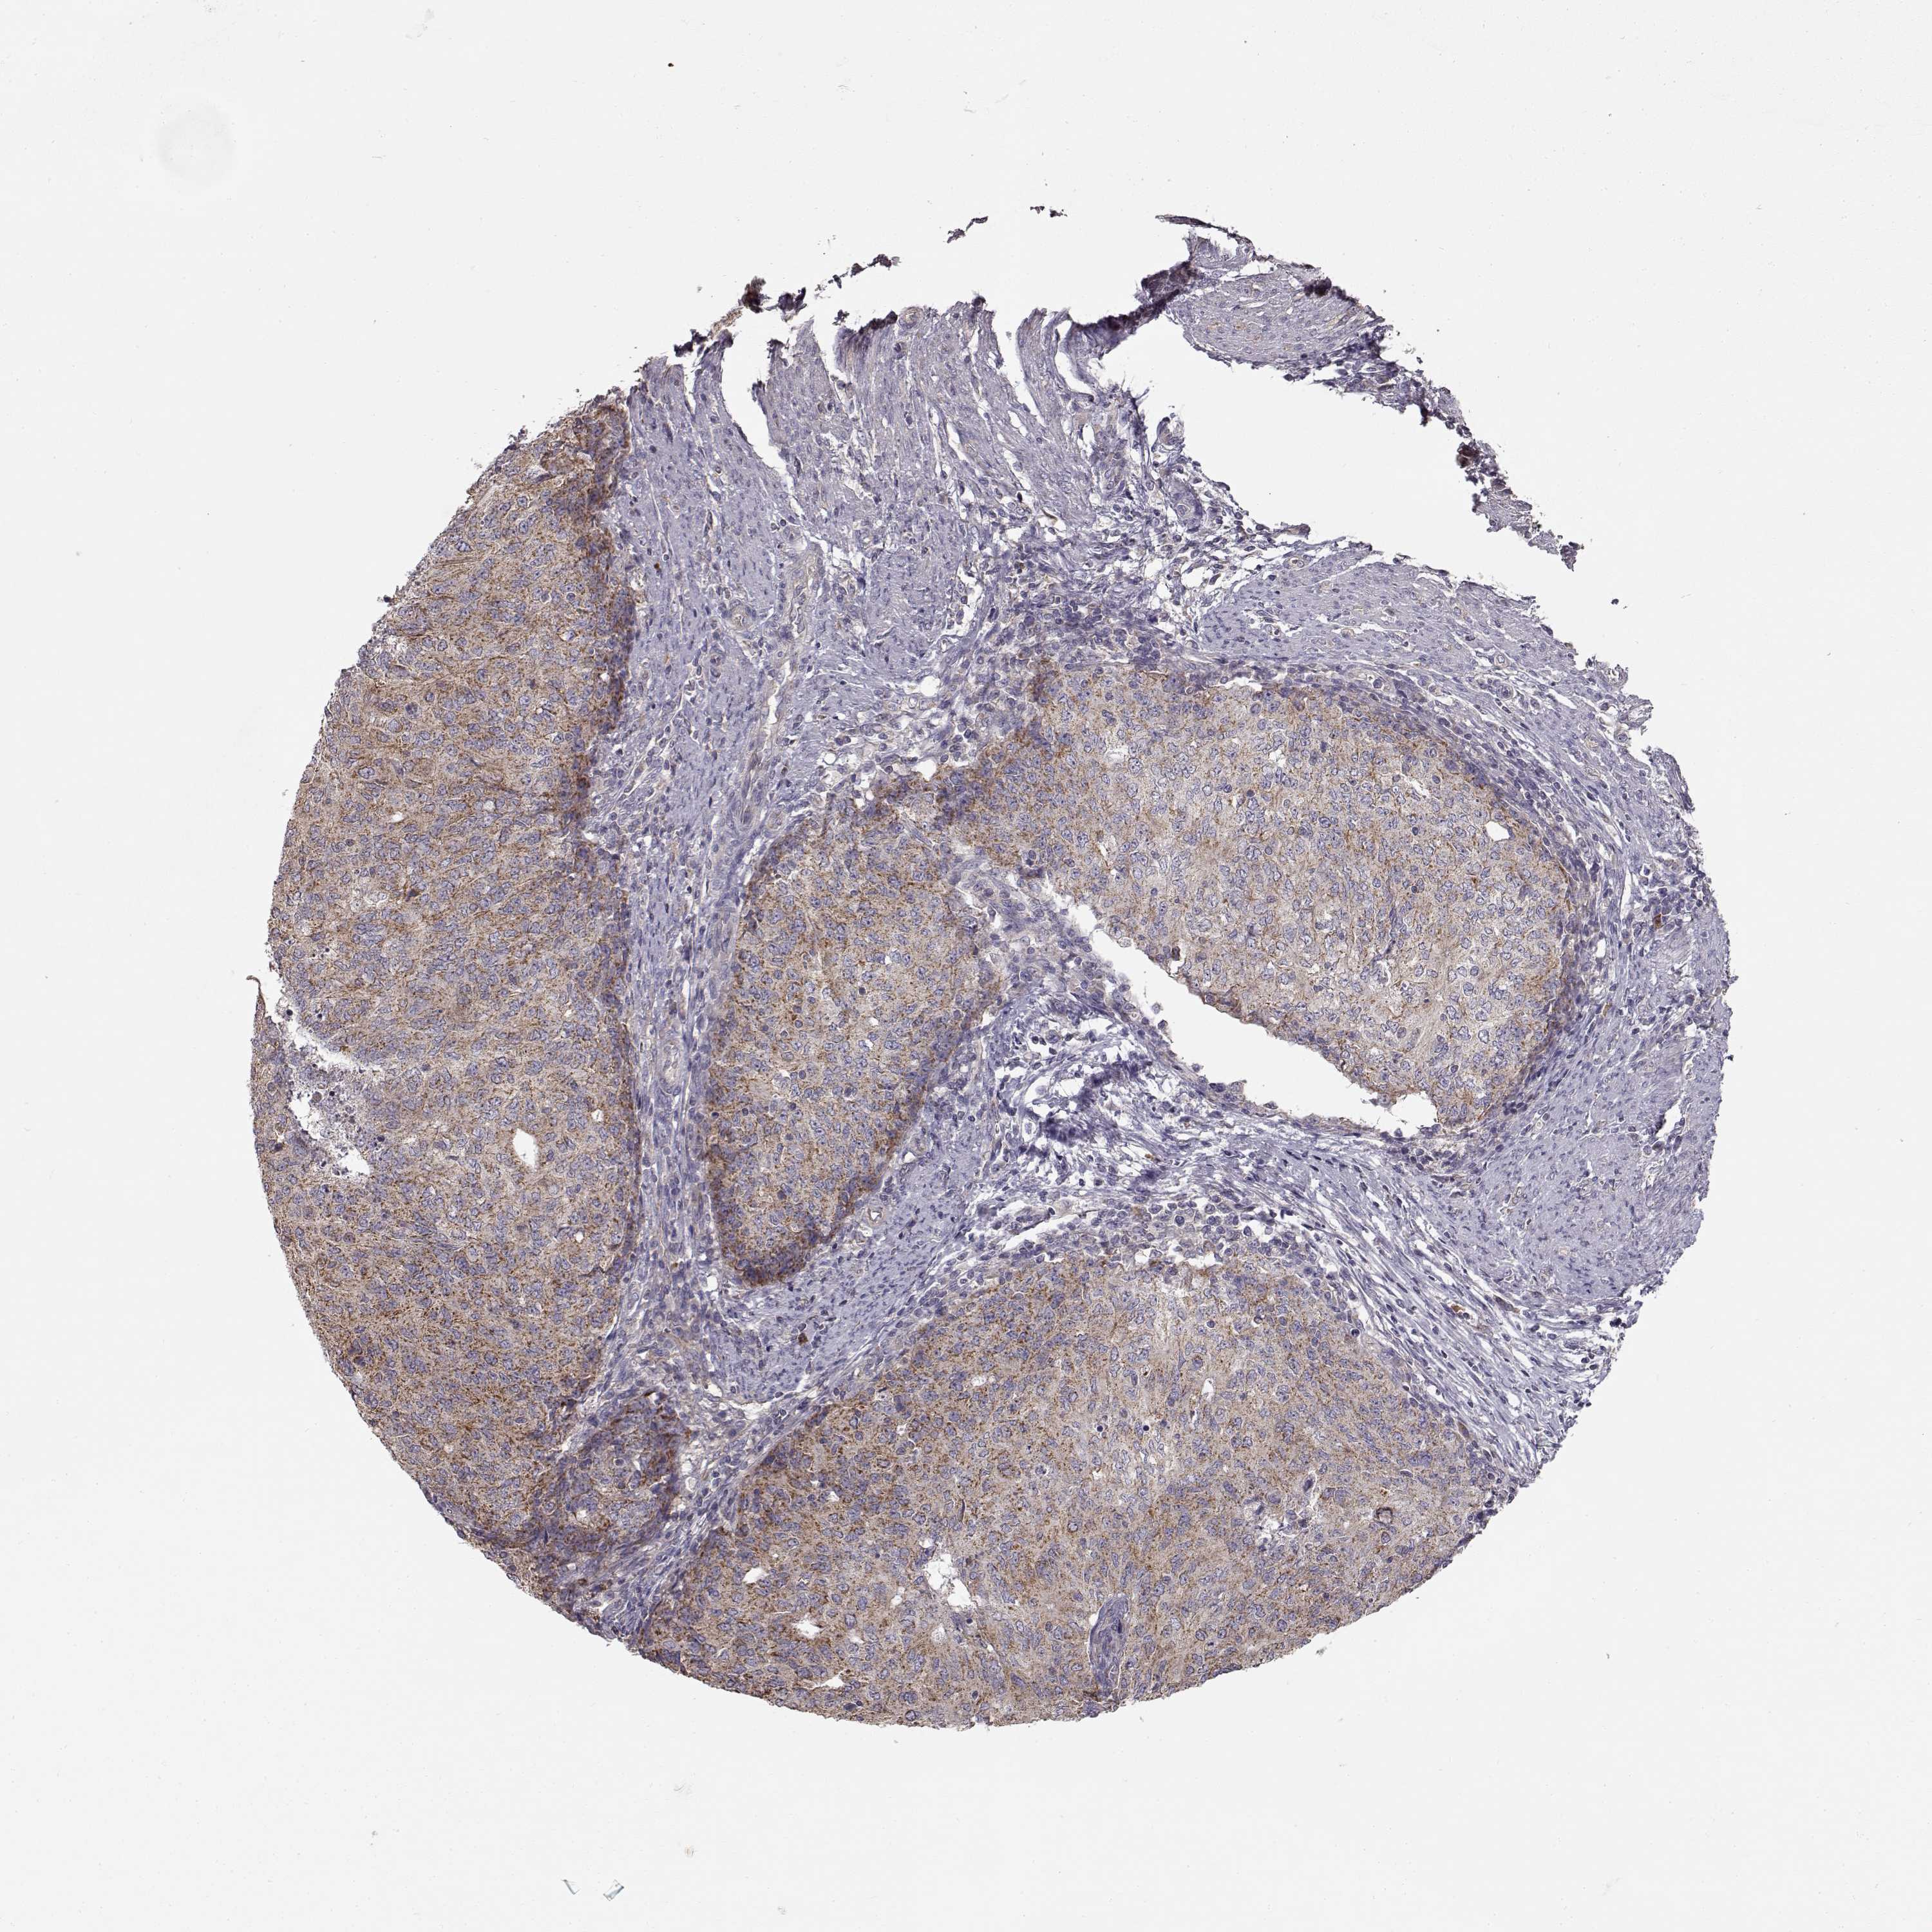

ENDOMETRIAL CANCER - Protein expressioni

A mouse-over function shows sample information and annotation data. Click on an image to view it in a full screen mode. Samples can be filtered based on level of antibody staining by selecting one or several of the following categories: high, medium, low and not detected. The assay and annotation is described here.

Note that samples used for immunohistochemistry by the Human Protein Atlas do not correspond to samples in the TCGA dataset.

Antibody stainingi

Antibody staining in the annotated cell types in the current human tissue is reported as not detected, low, medium, or high, based on conventional immunohistochemistry profiling in selected tissues. This score is based on the combination of the staining intensity and fraction of stained cells.

Each image is clickable and will lead to virtual microscopy that enables deeper exploration of all samples and also displays staining intensity scores, fraction scores and subcellular localization as well as patient and tissue information for each sample.

Antibody HPA045396

Antibody HPA070524

Antibody CAB025331

Staining

High

Medium

Low

Not detected

Intensity

Strong

Moderate

Weak

Negative

Quantity

>75%

75%-25%

<25%

None

Location

Nuclear

Cytoplasmic/membranous

Cytoplasmic/membranous,nuclear